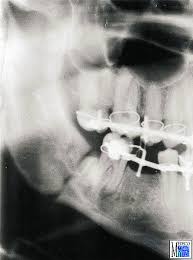

Frakturen Des Unterkiefers